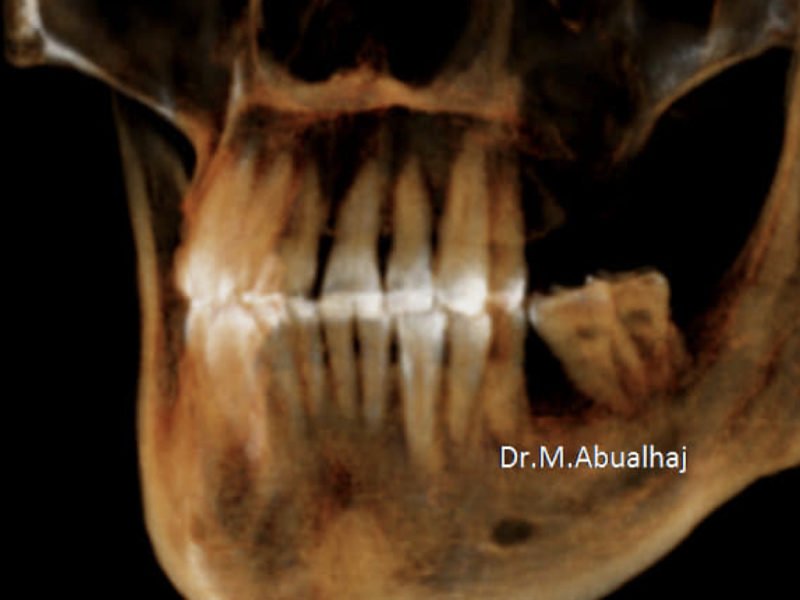

Patient's Data:

- Age: 51

- Sex: Female

- Smoker: No

- Pathologies: None

- Hygenic state: Good

- Alergies: None